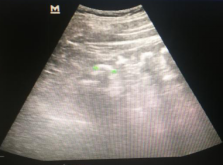

五天前感觉全身乏力,为求进一步诊疗,遂来我院检查:肌酐146umol/L、内生肌酐清除率50ml/min;肾脏超声:右肾103×52×48mm,左肾113×57×40mm,肾轮廓清楚,双肾皮质变薄,双肾满布多枚强光团(见图1),右肾较大者约22mm,左肾较大者约17mm,后伴声影,右肾显示一直径约6mm囊肿(见图1a、1b);肾脏CT:双肾实质内多发斑片状高密度灶;右侧肾盂类圆形高密度,边缘清晰,大小约1.5cm×1.2cm,肾盂轻度扩张,肾周围脂肪间质清晰(见图2a、2b)。

1a

1b

超声探测到钙化和结石的非特异性声像图,髓质回声增强。